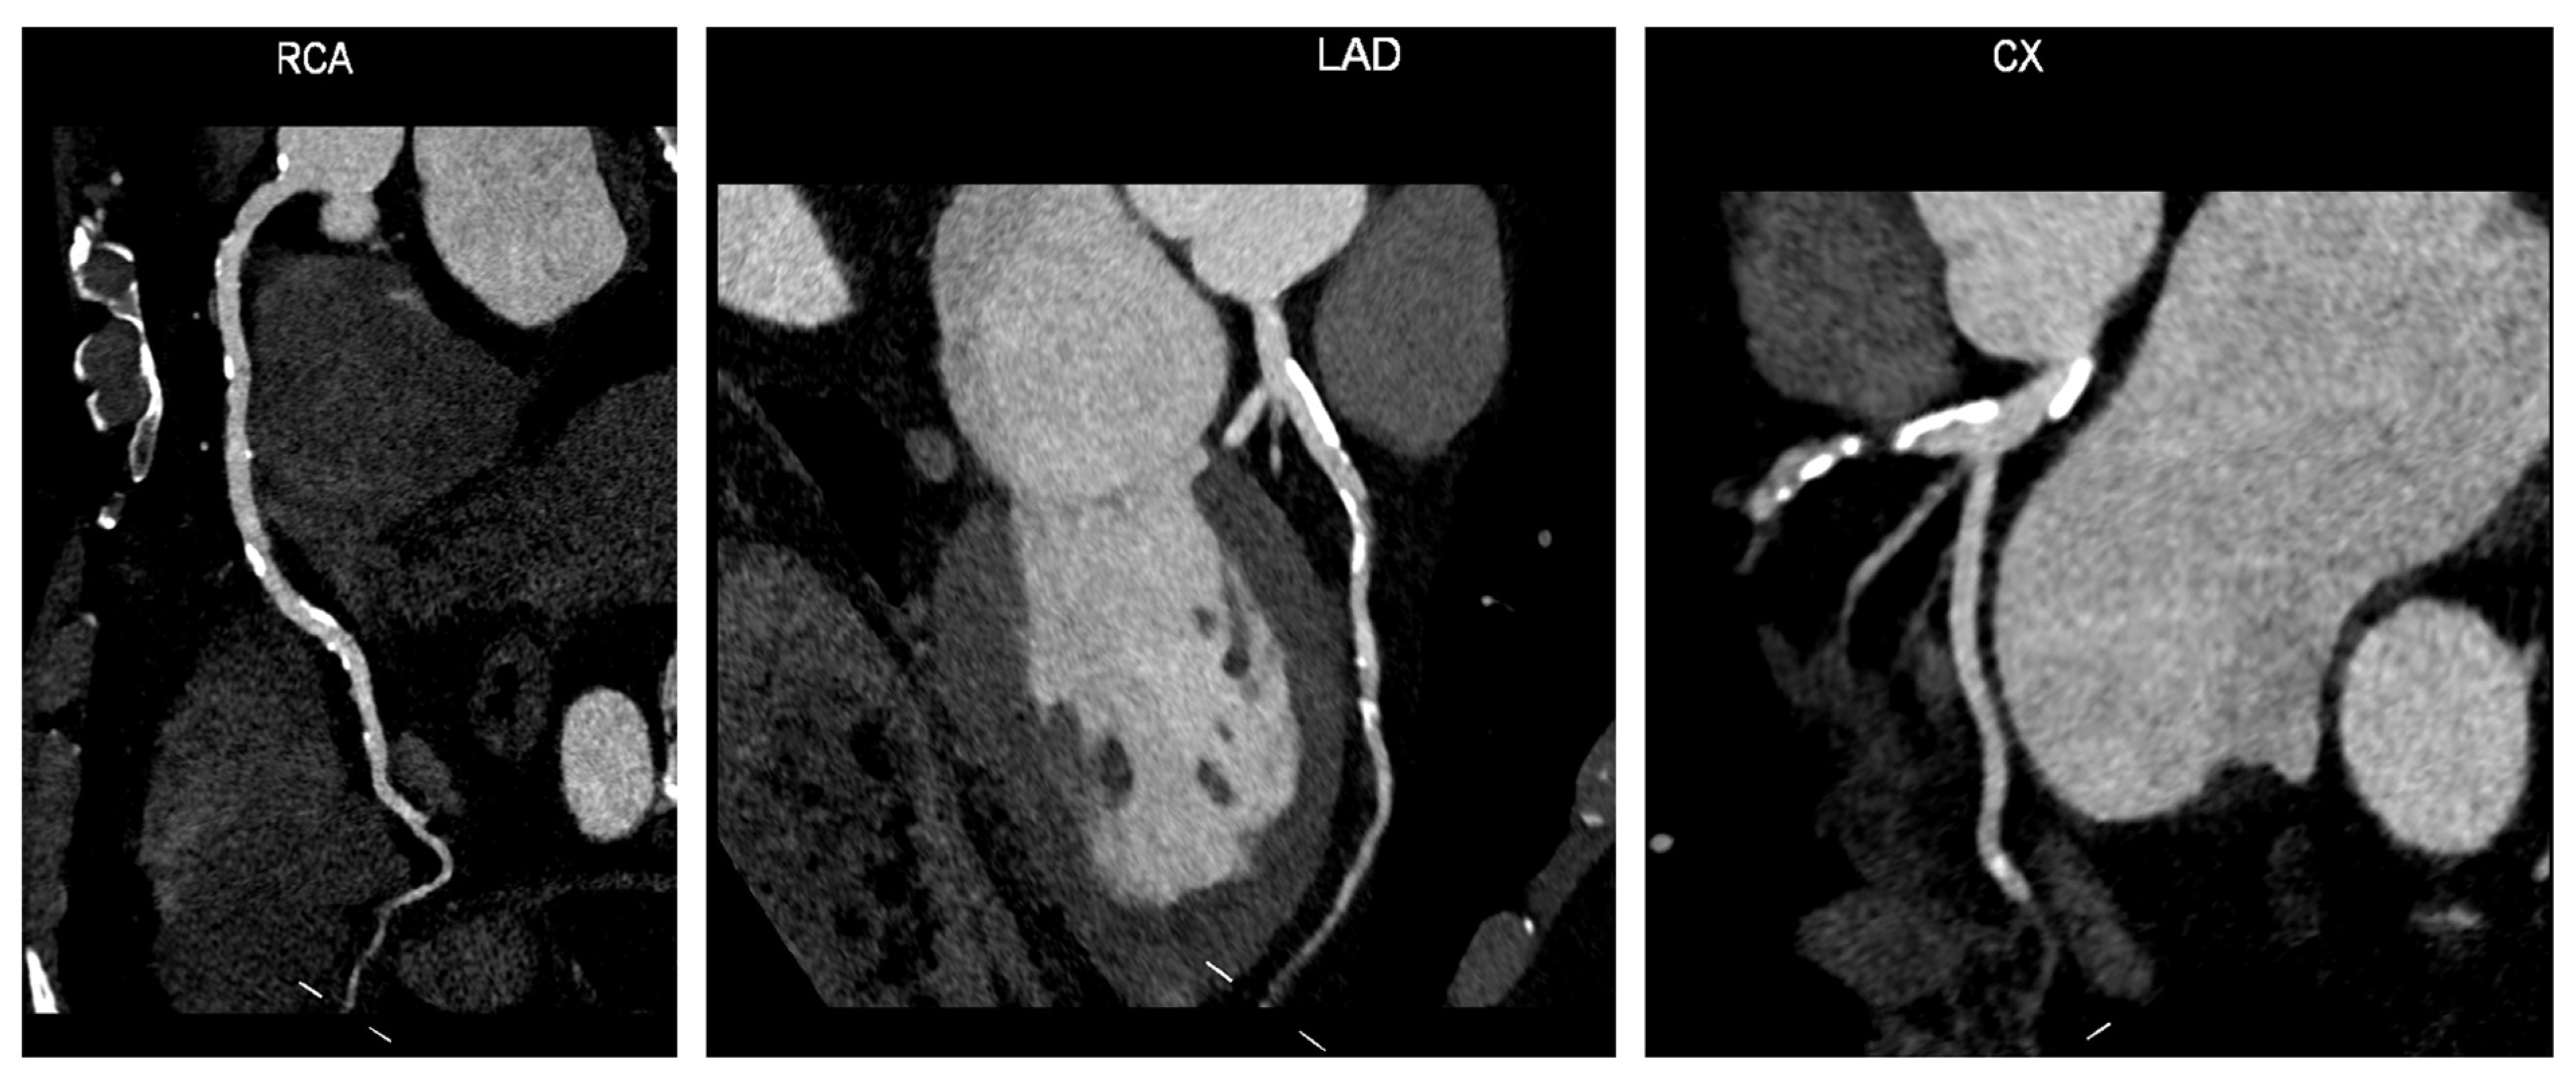

7. Coronary Artery Calcium Score